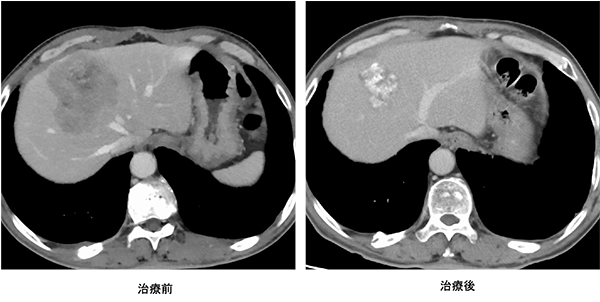

政府の「がん医療の均てん化政策(https://www.mhlw.go.jp/stf/shingi/other-kenkou_128568.html)により、多くの病院で良質ながん医療を受けることができるようになってきました。近年では、地域の拠点となる病院では、より高度で専門的ながん医療を行うことを目指した「がん医療の集約化」が重要視されています。そうした中、私達は本邦のガイドライン(https://www.jsccr.jp/guideline/index.html)だけではなく、欧米のガイドライン(https://www.nccn.org/guidelines/category_1)、(http://interactiveguidelines.esmo.org/esmo-web-app/toc/index.php?subjectAreaId=3&loadPdf=1)や大規模な臨床試験など、常に最新のがん治療にアンテナを張り、その時点で最良と思われる治療を提供できるように努めています。また、他の病院では手術ができないと言われたような場合や人工肛門が必要だと言われた場合でも、本当にできないのか、人工肛門を回避できる方法はないのかなど、内科や放射線科、病理診断科など、がんを専門とする複数の診療科とともに合同カンファレンスを行い、最適な治療法を常に模索しています(図1-5)。

ロボット支援下手術により安全に吻合できるようになったため人工肛門が回避できた。